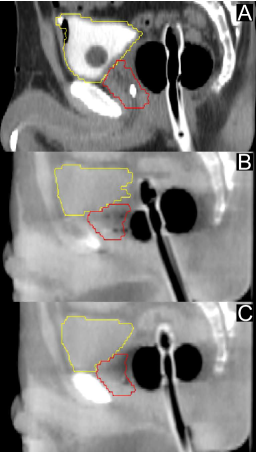

Figure 2: Saggital slices of the pelvis showing the prostate (red), bladder (yellow), and effect of ERB intervention. A) pCT image showing radiotherapy planning position. B) CBCT image showing pre-intervention ERB position. The ERB was not inserted to the same depth as it was for the pCT scan, and also exhibits a relative tilt. The shape of the prostate is noticeably different. C) CBCT image showing post-intervention ERB position, which more closely matches the pCT image.

For 24 of the 35 treatment fractions (69%), the initial ERB placement was clinically judged to be insufficient during localization to allow maximization of PTV coverage and organs-at-risk (OAR) sparing using only rigid-body translations. For instance, it was seen in some cases that the CBCT prostate extended outside the superimposed PTV contour. In other cases, misalignment of the anterior ERB edge after alignment of the fiducial markers was observed. For these cases, the position of the ERB was manually re-adjusted to achieve better alignment. An overview of the target and OAR geometry is shown in Fig. 1, and an example ERB intervention is shown in Fig. 2. In total, there were 24 pre-intervention image sets, 24 post-intervention sets, and 11 fractions where no intervention occurred. The act of intervening added roughly 5-15 minutes to the total patient setup time.